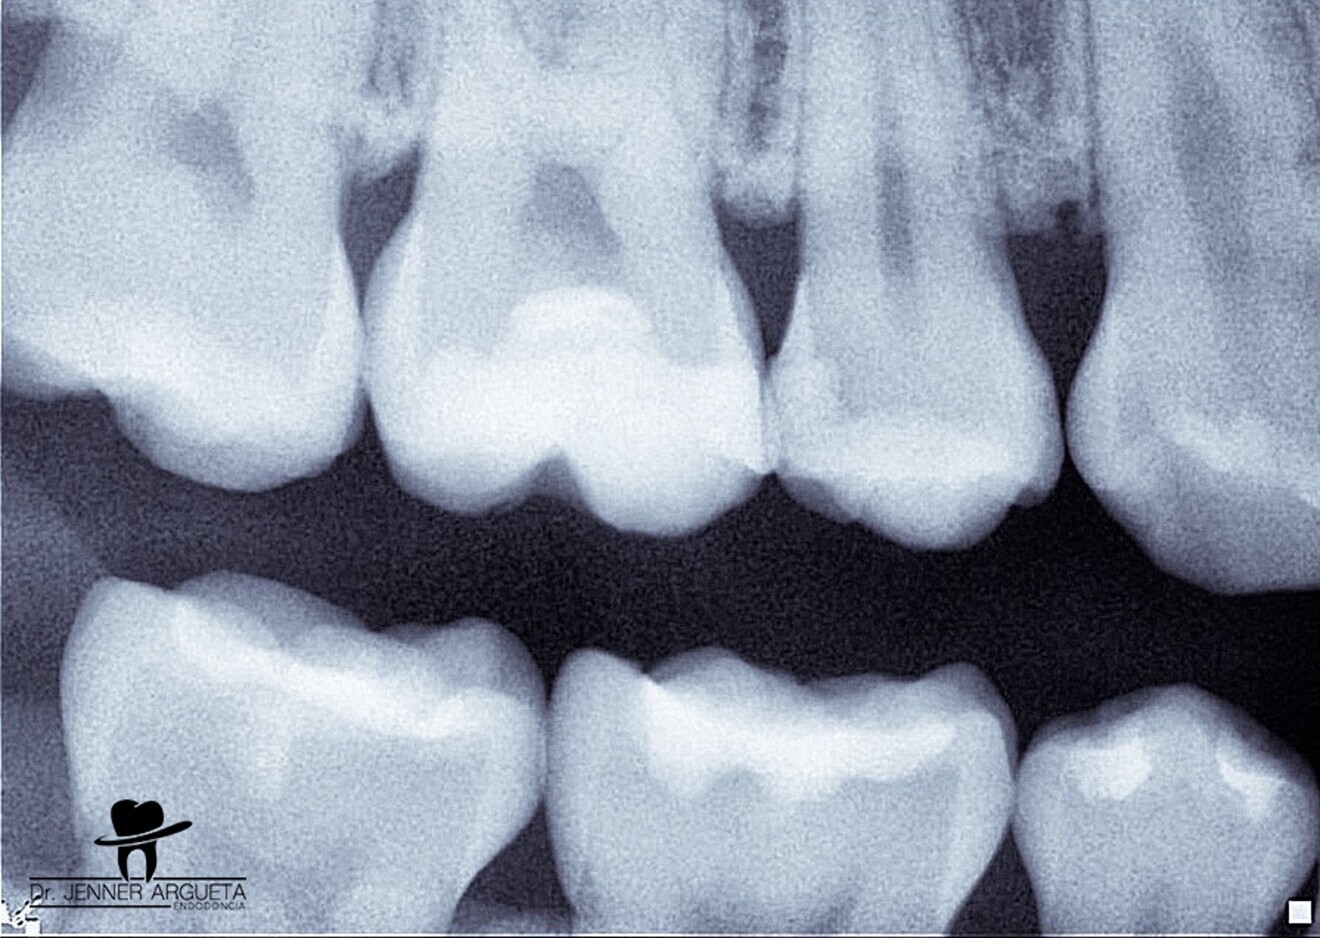

Fig. 2: Bitewing radiograph showing evidence of a deep restoration in tooth #16 at mesial level. Under-mineralised tissue was found close to the mesial pulp horn.

The patient attended reporting short-term pain in tooth #16 (Fig. 1). Through radiography, clinical assessment and an analysis of the patient’s clinical history, reversible pulpitis was diagnosed, and a deep Class II temporary restoration was found (Fig. 2).